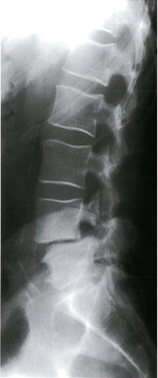

X-ray lumbar spine (lateral view)

Anterior displacement of L4 on L5 is visible. In addition, there is degenerative disk disease with narrowing of the L4–L5 disk space.